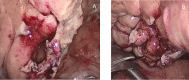

We present a case of a 79-year-old man with lower abdominal pain and negative Blumberg sign. An indwelling bladder catheter was inserted for urinary retention due to a tight phimosis 2 months earlier. A contrast-enhanced computed tomography scan revealed a huge gastrectasia and small bowel distention due to a suspected adherent bridle. The clinical signs and the laboratory tests were highly suspicious for bowel obstruction and emergency surgery was indicated. Exploratory laparoscopy showed a bladder hole tamponade by an ileum loop. The perforation was sutured laparoscopically and the patient was discharged on the 14th postoperative day. In our case, emergency laparoscopic exploration was useful for the diagnosis and the treatment of spontaneous bladder rupture. We hope this case report can be useful to give these patients better outcomes. Notably we would like to emphasize that the presence of a urinary catheter can be a risk factor for intraperitoneal bladder rupture.